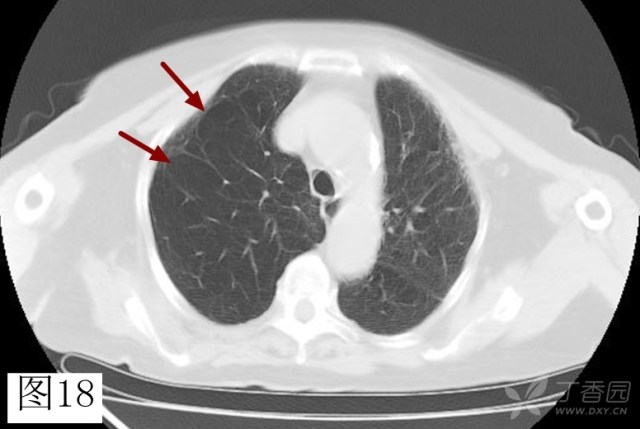

间隔旁型肺气肿

图片尺寸528x397